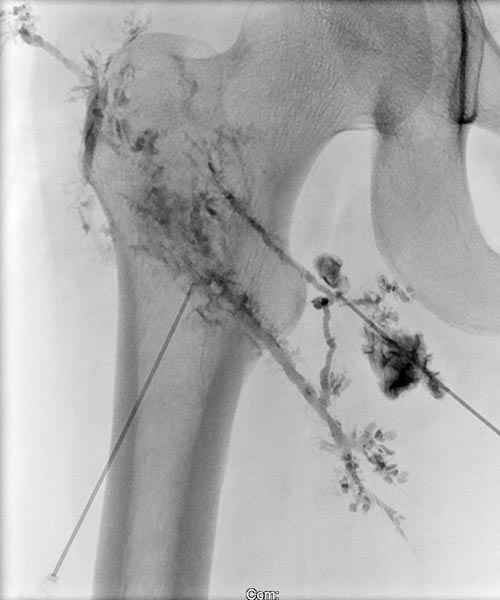

Image of direct lymphography with water-soluble contrast medium in direct puncture technique under sonographic guidance.

Here, it was possible to puncture the dysplastic, dilated lymphatic channels of the lymphatic malformation in the subcutaneous tissue several times.

Picibanil (OK-432) was then injected into these channels as a sclerosing agent to seal the cutaneous dysplastic lymphatic channels via the inflammation.

Lymphography in direct puncture technique under sonographic guidance.

The subcutaneous lymphatic vessel system is severely dysplastic, partially enlarged and showing bizarre net-like dilation. Normal lymphatic vessels are significantly smaller.

Again, picibanil (OK-432) was injected for inflammation-induced lymphatic vessel sclerotherapy and skin sealing.